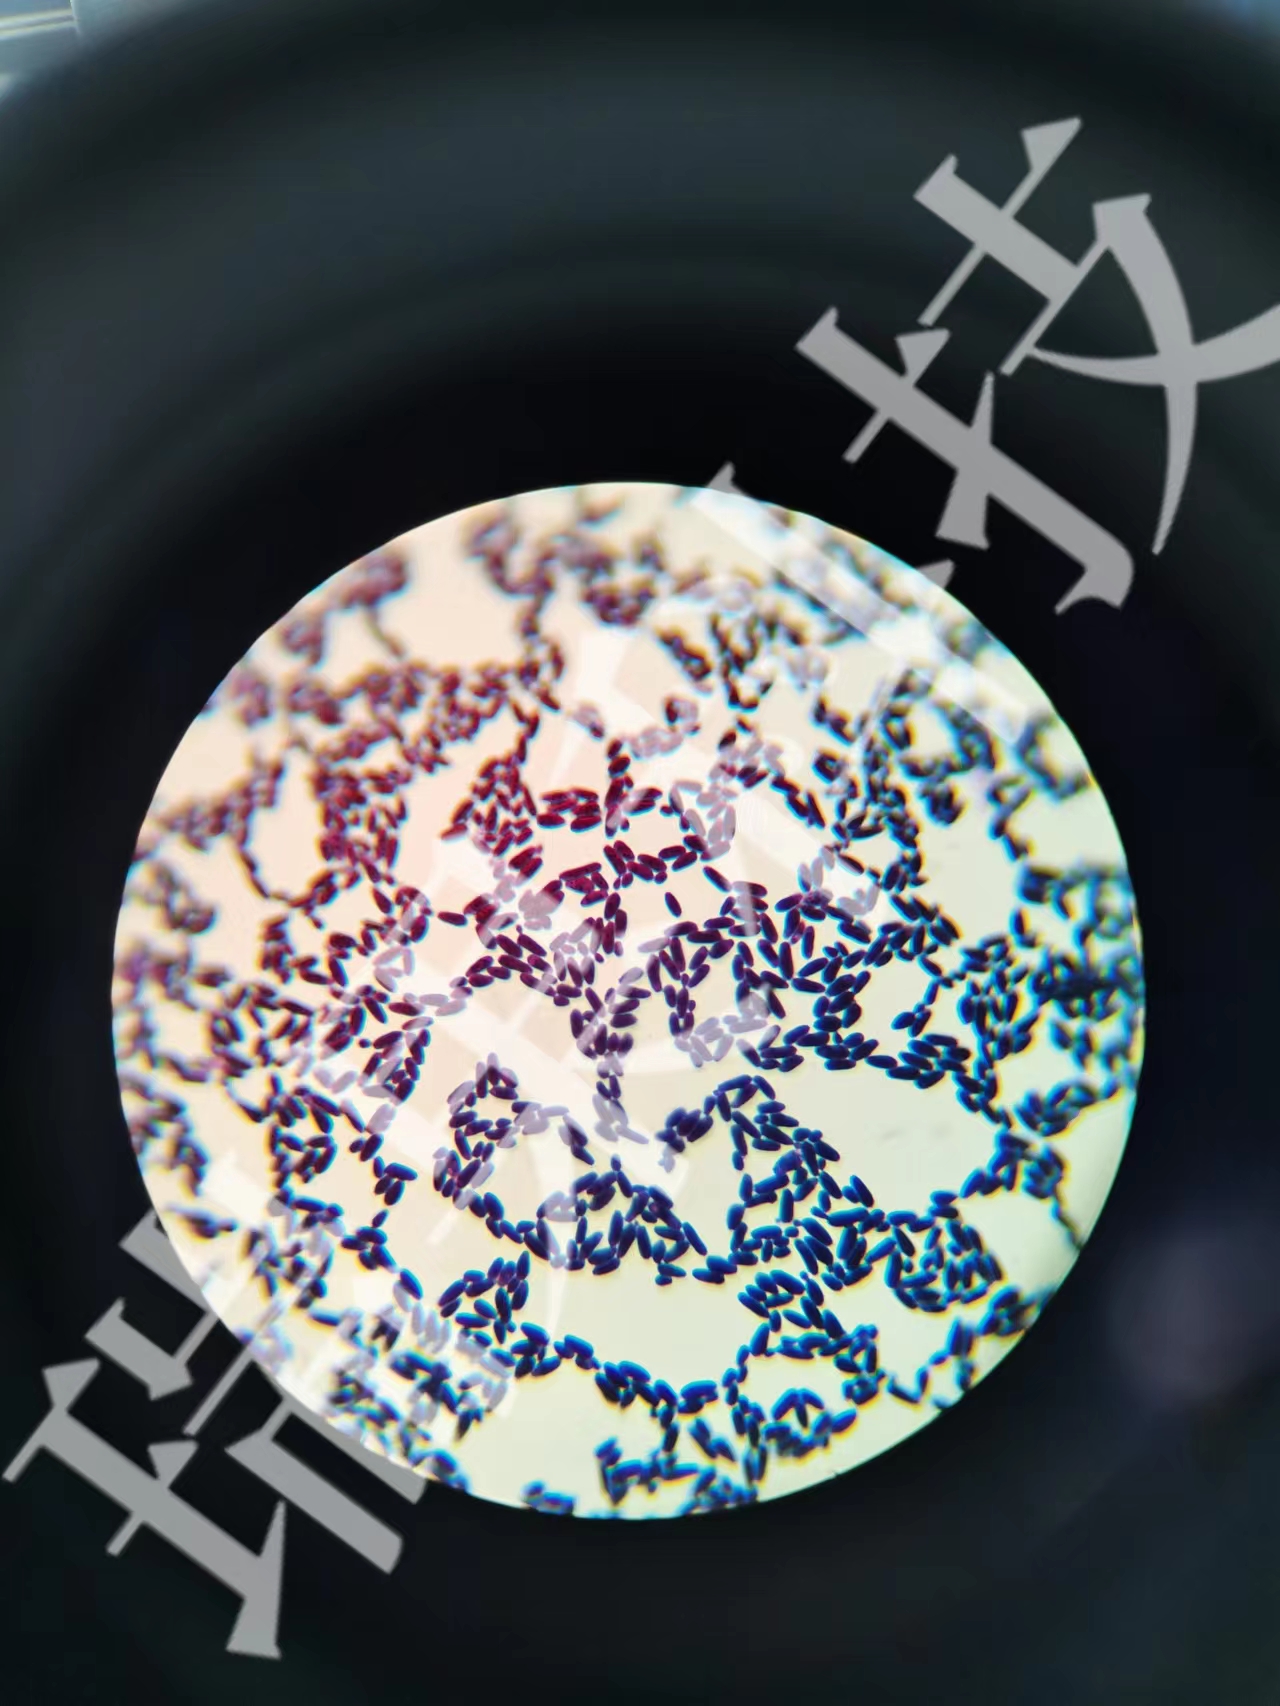

苏丹染色

苏丹染色:Warthin-Starry银染色是Warthin和Starry在1920年用于显示螺旋体的染色法,其染色原理在于螺旋体表面的黏蛋白与银结合,呈黑色。